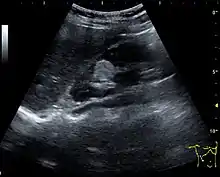

US is useful for diagnostic and prognostic purposes in chronic kidney disease. Whether the underlying pathologic change is glomerular sclerosis, tubular atrophy, interstitial fibrosis or inflammation, the result is often increased echogenicity of the cortex. The echogenicity of the kidney should be related to the echogenicity of either the liver or the spleen (Figure 22 and Figure 23). Moreover, decreased renal size and cortical thinning are also often seen and especially when disease progresses (Figure 24 and Figure 25). However, kidney size correlates to height, and short persons tend to have small kidneys; thus, kidney size as the only parameter is not reliable.[1]

- Figure 22. Chronic renal disease caused by glomerulonephritis with increased echogenicity and reduced cortical thickness. Measurement of kidney length on the US image is illustrated by ‘+’ and a dashed line.[1]

- Figure 23. Nephrotic syndrome. Hyperechoic kidney without demarcation of cortex and medulla.[1]

- Figure 24. Chronic pyelonephritis with reduced kidney size and focal cortical thinning. Measurement of kidney length on the US image is illustrated by ‘+’ and a dashed line.[1]

- Figure 25. End-stage chronic kidney disease with increased echogenicity, homogenous architecture without visible differentiation between parenchyma and renal sinus and reduced kidney size. Measurement of kidney length on the US image is illustrated by ‘+’ and a dashed line.[1]